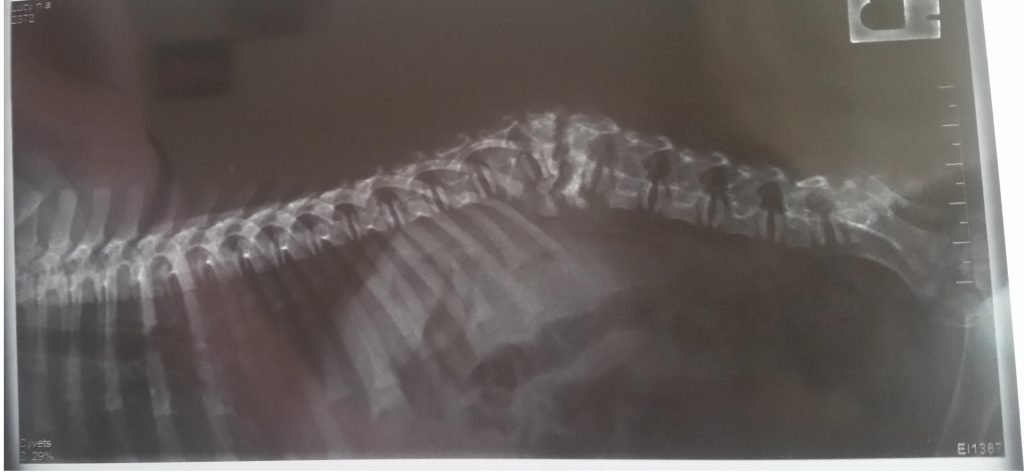

Va atașez radiografia .

Am sa va trimit câteva filmulețe cu cãțelușa, poate chiar astãzi. Mãduva nu a fost afectata, doar nervii periferici. Când am luat-o am fost la mai multi doctori, unii chiar cu renume, care mi-au recomandat eutanasierea ei, spunând ca nu au ce sã-i facã. Îmi spuneau ca e pãcat sa se chinuie și ea, și eu. As dori acum sa le arat acestor doctori cum este ea acum. Am multe radiografii. Aveți cumva site în limba engleza ? Ar fi mai ușor sã-i dau doctorului sa citeascã mai multe.